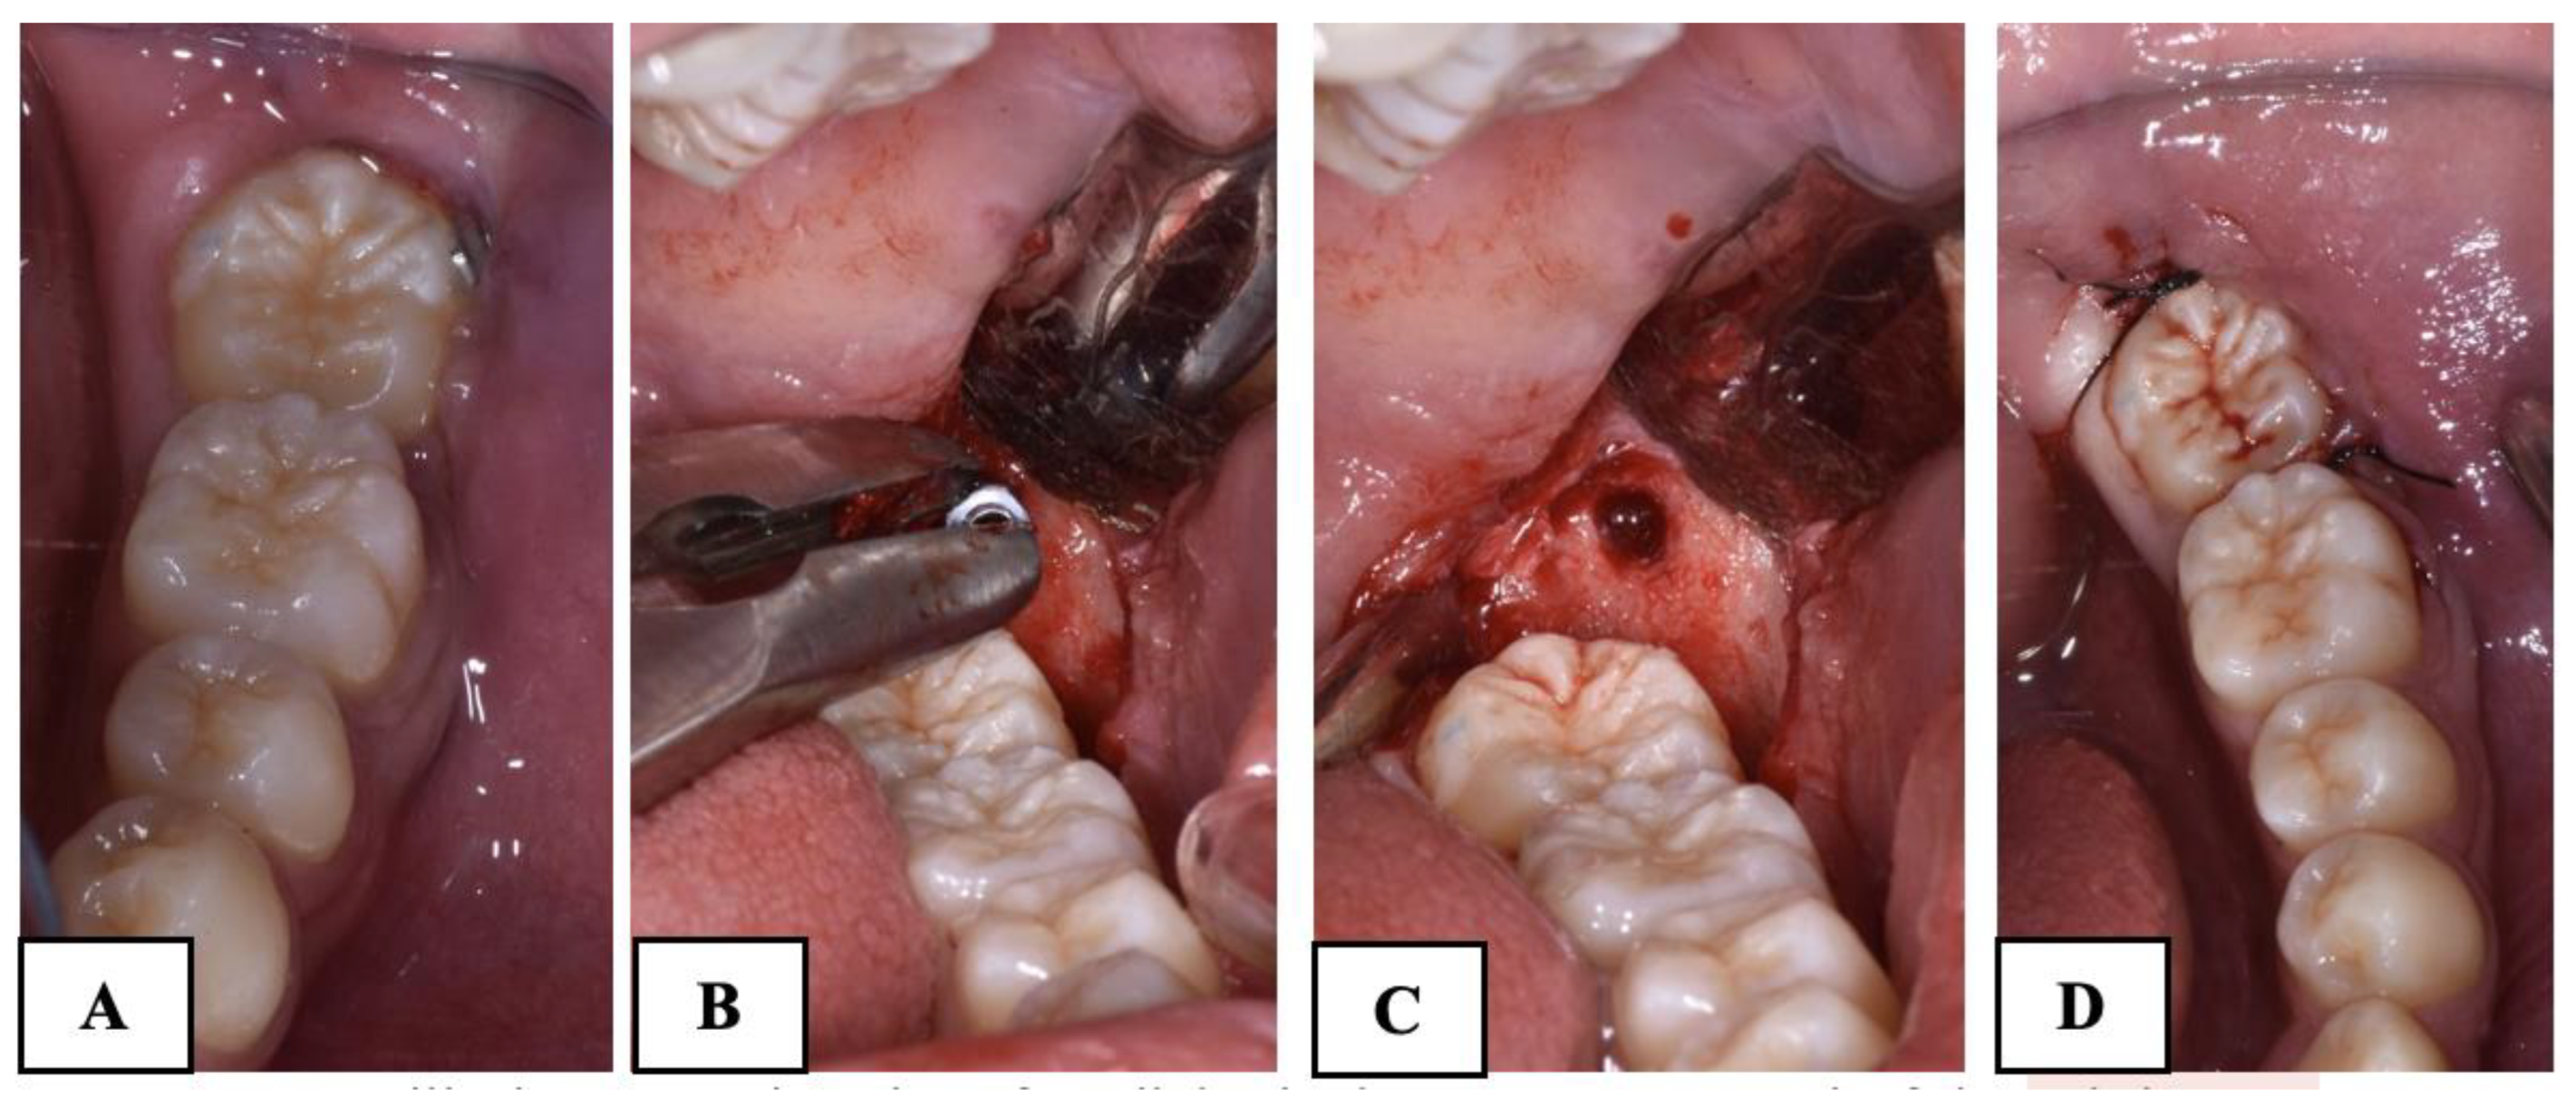

For the subjects treated with the traditional brass wire technique (Group A), follow-up visits were scheduled every 20 days, during which wire activations were performed until the uprighting of the MM2 was complete. In contrast, the Group B subjects had monthly follow-up visits until the complete uprighting of the MM2. The difference in the follow-up between the two groups is due to the need to periodically activate the brass wire to ensure the continuous movement of the MM2. In Group B, a longer follow-up was implemented because it was not necessary to reactivate the elastic chain. However, it remained important to monitor the patient for any potential complications, such as mini-implant failure or the detachment of the orthodontic button. In all cases treated with skeletal anchorage, there was no need to replace or reactivate the elastic chain, significantly reducing discomfort for the subjects. No miniscrew stability issues were observed in the Group B participants. The treatment was considered completed when the mesial marginal ridge of MM2 had passed the point of contact with the distal marginal ridge of MM1. The treatment time was recorded. A radiographic control was made before removing the orthodontic appliance in both groups (Figure 4). The advantages and disadvantages of the two techniques are shown in Table 1.

The brass wire, miniscrew, and orthodontic brackets were removed at the end of the treatment (Figure 5).

Figure 5. (A): Mandibular second molar after disimpaction; (B,C): removal of the miniscrew; (D): suture.